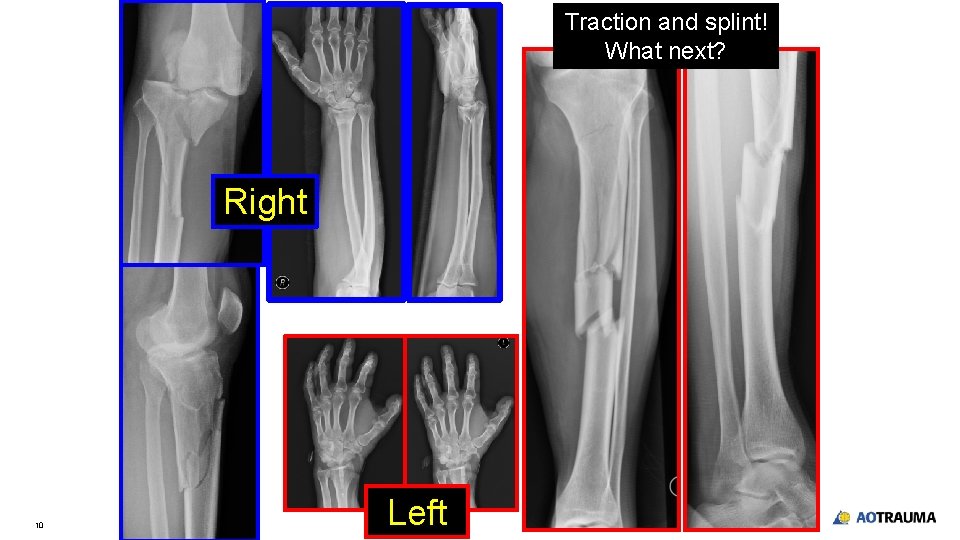

Traction and splint! What next? Right 10 Left